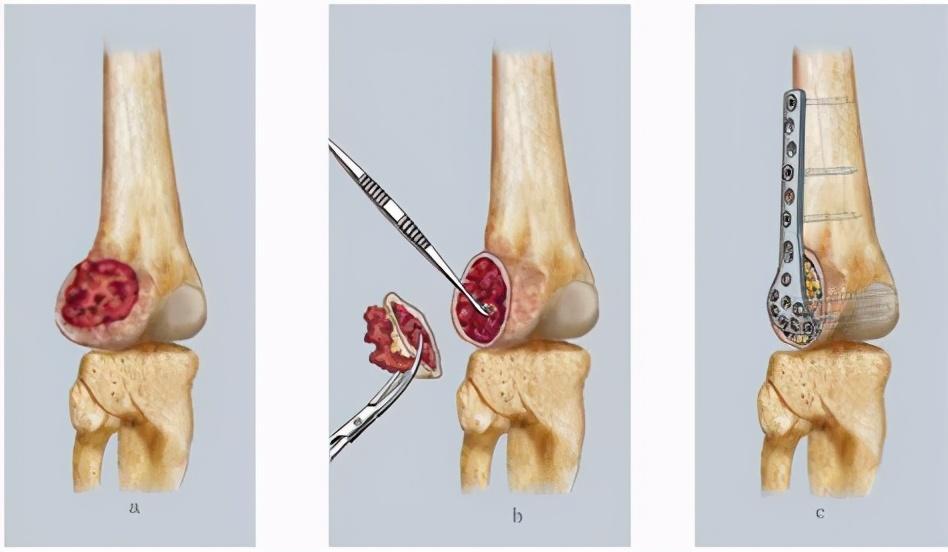

五、有一个大包:肿瘤。

当然在一些非常罕见的情况下,患者既不是腰椎间盘突出,也不是动脉和静脉的问题。

这类患者往往会在皮肤下面摸到一个硬硬的包块,也就是说在双侧腿部长东西了,这个东西有可能是良性的,也有可能是恶性的,如果是恶性的那就可能是肿瘤了。

特别是其他部位肿瘤转移过来的,我们称之为转移癌,有的时候就是在腿上先发现的。

去医院的时候要去骨科看一下,如果发现不是好东西应该去肿瘤科再看一下。